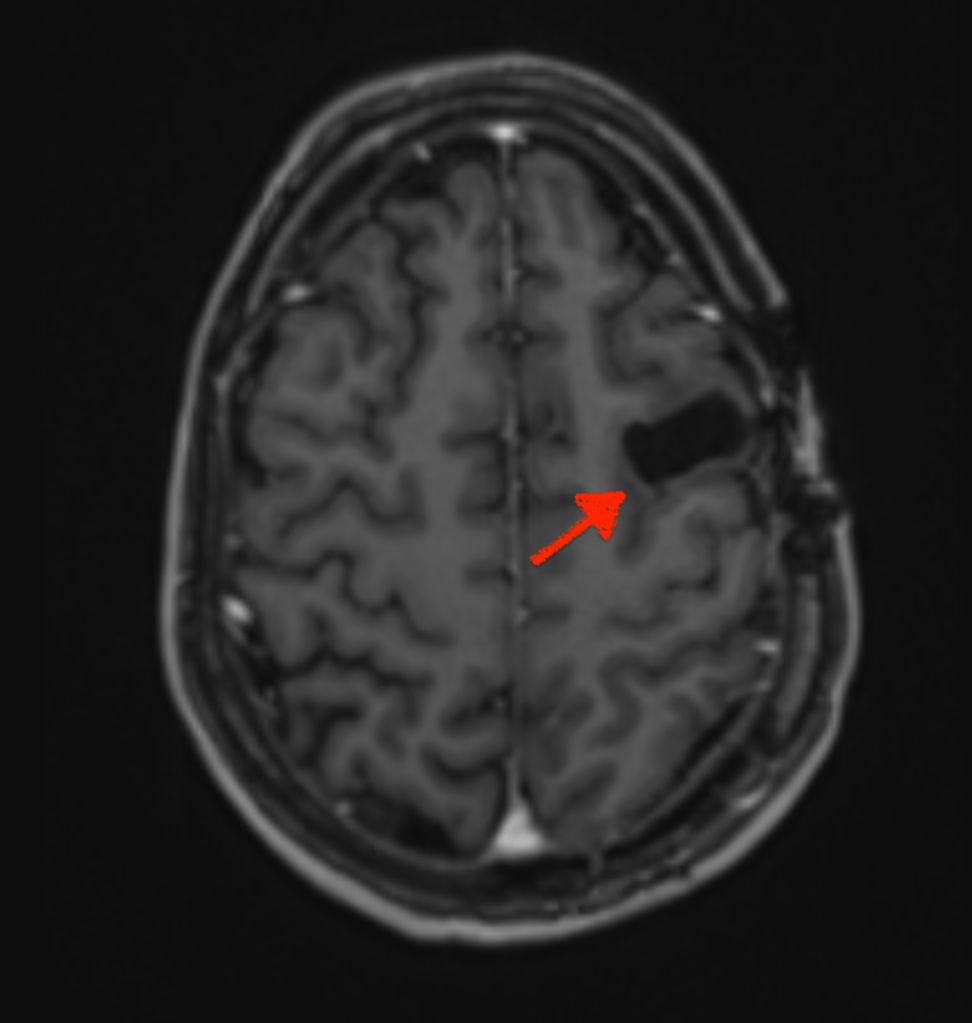

Zoë and only Zoë (as one of her oncologists reminded me) can decide. My role as advocate is to research treatments, make flow charts and advise her. She can, of course take advice from others; I guess doctors would be a good start. Sometimes, I have lost sight of her ability to make the right decision for herself; maybe focusing on the fact that she has had two chunks of her brain removed and acquired a brain injury in the process. Shocking as these images are, the surgeon may have removed the neurons that processes her right peripheral vision; but not her ability to make a decision. The brain is a fascinating organ.